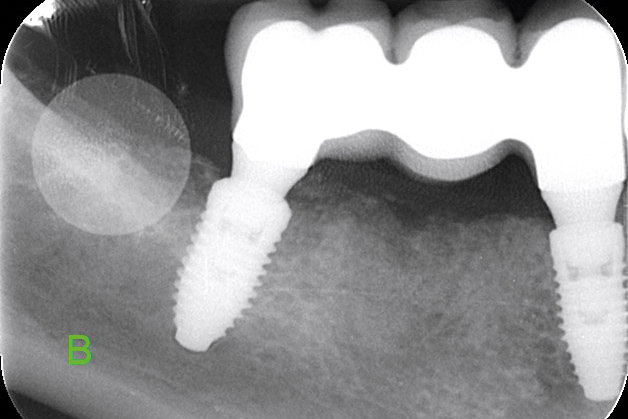

Multiple socket preservation in the mandibular with collacone® max – Dr. D. Jelušić